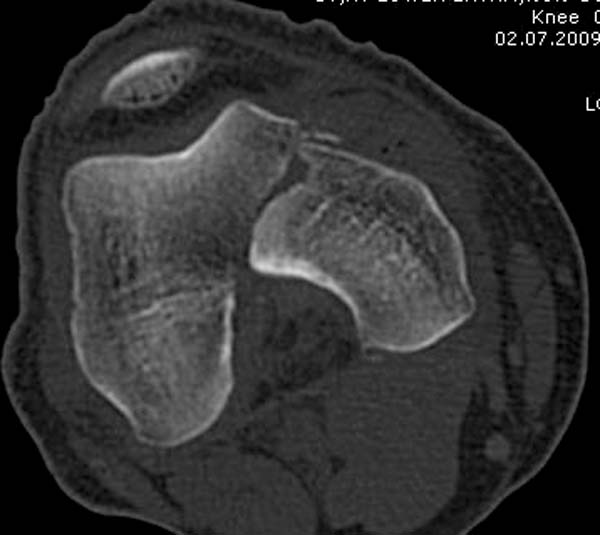

[Ortho] Нелеченный перелом Hoffa

Здесь представлены различные варианты фиксации перелома, а также снимки

комбинации перелома с повреждением хряща (12-19). Пластика хряща

OsseoFit и установка custom made plate.